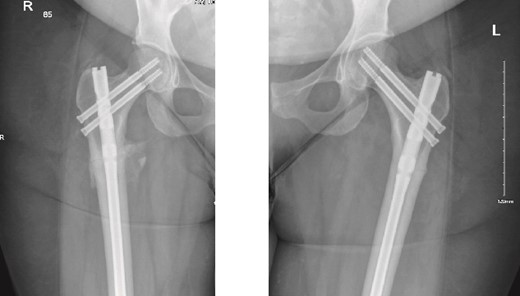

The patient was seen in the clinic at 2 weeks, 6 weeks, and 6 months post-surgery. She was doing well, reporting only mild pain. She was fully weight-bearing with the assistance of a cane and had good range of motion (Figs 3 and 4).

6-weeks follow-up anteroposterior (AP) view of the right and left femurs after CRIF with IM nail.